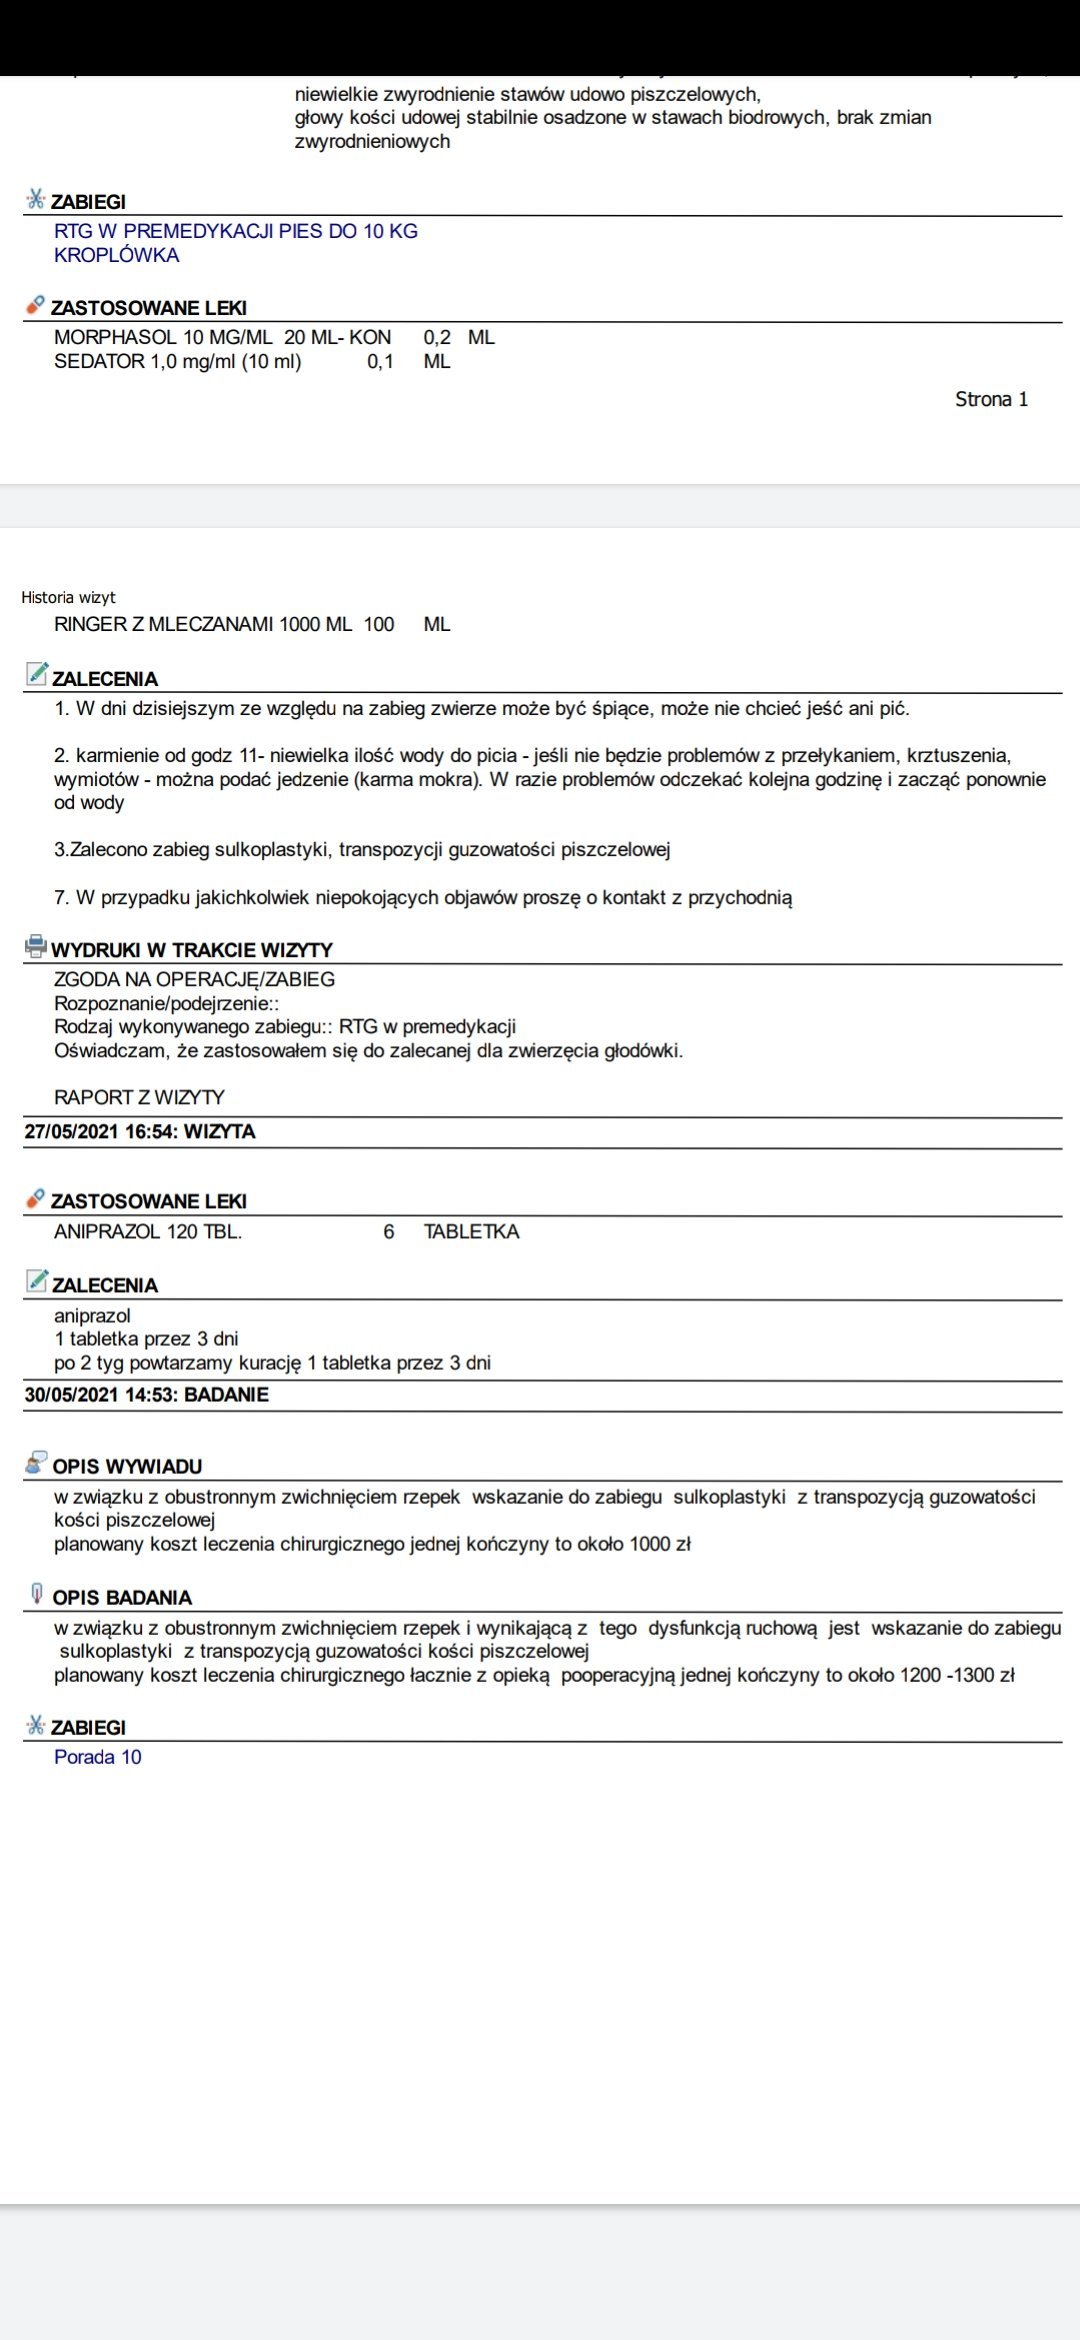

Dwa lata temu Angie wróciła ze spaceru z tatą kulejąc. Oczywiście niezwłocznie pojechałam z nią do weterynarza. Lekarz zbadał ją palpacyjnie i stwierdził zwichnięcie rzepek w obu stawach 2-ego i 3-ego stopnia. Dowiedziałam się, że jedynym wyjściem z tej sytuacji jest zabieg kosztujący dobre 3000zł, których oczywiście w wieku 19 lat absolutnie nie miałam, a moich rodziców nie było na to stać.

Rok później zmieniłam lecznicę, w której przyjmuje ortopeda. Angie nie używała prawej tylniej łapki schodząc po schodach, a że ciągle wyskakiwały jej rzepki, zaczęła usztywniać łapki, by się przed tym uchronić. Postanowiłam jeszcze raz spróbować, być może ten lekarz postawi inną diagnozę, znajdzie inne rozwiązanie. Ponownie przy jedynie badaniu palpacyjnym (bez zdjęć RTG, ponieważ lekarz twierdził, że nie są potrzebne w tym przypadku) stwierdzono zwichnięcie rzepek w obu stawach 3-ego i 3/4-ego stopnia. Wtedy wiedziałam, że jeśli jest możliwość wykonania zabiegu, to stanę na głowie żeby uratować swojego psa od bólu. Weterynarz stwierdził jednak, że zabieg w tym wieku może być ryzykowny (mimo idealnych wyników krwi), a nie przyniesie spodziewanych rezultatów, więc 3 miesiące temu zdecydowałam się na zabieg ostrzykiwania stawów kolanowych kwasem hialuronowym, żeby choć trochę zwiększyć komfort życia i poruszania się Angie.

Na nasze szczęście wraz z początkiem maja dostaliśmy możliwość odbywania raz w tygodniu zajęć praktycznych na uczelni w Bydgoszczy. Jako, że mieliśmy opcję przyprowadzić na zajęcia własne zwierzęta i na nich ćwiczyć, zabrałam ze sobą moją Angie. Już na pierwszych zajęciach sunia pokazała dużą bolesność mięśni grzbietu. Tydzień później przy próbach masażu kończyn miednicznych psinka zareagowała agresywnie, od razu dała znać, że nie chce być tam dotykana. Na naszej uczelni przyjmuje fizjoterapeuta zwierząt, więc postanowiłam zaprowadzić tam swojego psa. Okazało się, że mięśnie tylnich łap i kręgosłupa są tak pospinane, że wywołują bardzo dużą bolesność. Przez odciążanie prawej (gorszej) łapki, mięśnie lewej są ciągle spięte, obolałe, przeciążone. Zaczęłyśmy działać przeciwbólowo i rozluźniająco poprzez laseroterapię, ultradźwięki i magnetoterapię. Pani zoofizjoterapeutka poleciła mi jeszcze zrobić dokładne zdjęcia RTG w jednej z bydgoskich klinik (ponieważ bez nich ciężko było wykluczyć bądź potwierdzić wskazania do zabiegu).

Nie zamierzałam się poddać i jeszcze w tym samym tygodniu pojechałam do kliniki Sweetvet na zdjęcia i konsultacje. Okazało się, że mimo tak dużej przestrzeni czasowej od wstępnej diagnozy stawy kolanowe Angie nie są w tragicznym stanie: lewa rzepka-zwichnięcie 2-ego stopnia, prawa- 3-ego. Zdjęcia RTG wykazały zwyrodnienia rzepki i głowy kości udowej w obu kończynach. Bez zabiegu sulkoplastyki i transpozycji guzowatości kości piszczelowej pogłębiające się z czasem zwyrodnienia doprowadzą do zerwania więzadeł. Doktor potwierdził, że Angie jako zdrowy pies, z dobrymi wynikami jak najbardziej nadaje się do operowania, tym bardziej, że teraz jesteśmy w stanie kolosalnie zmienić jej komfort życia.